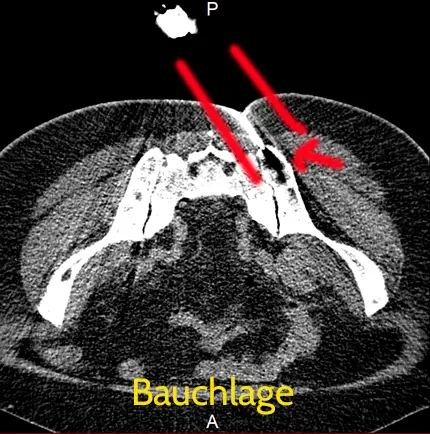

CT - Bilder der Punktion des Beckenkamm

Punktion

Punktion unter CT